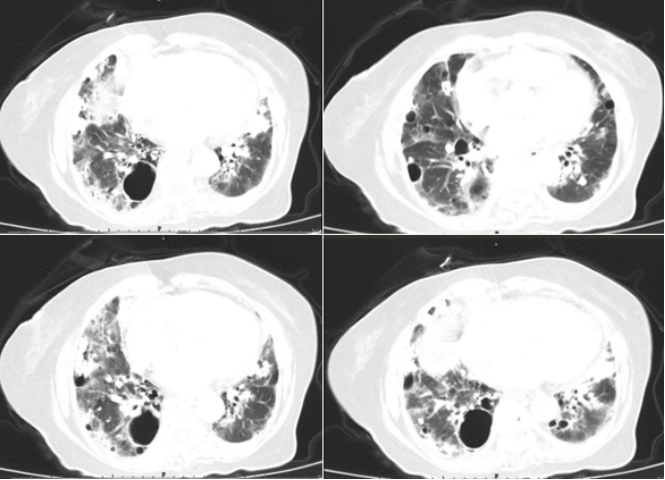

患者入院3周前不慎受凉后出现畏寒、发热,最高体温39.3℃,稍咳嗽,少量白黏痰,近日为黄脓痰,活动后气喘。入院前2周上述症状明显加重。4月21日至我院急诊就诊,胸部CT示两肺明显磨玻璃样渗出,伴多发气囊表现(图1)。予“头孢曲松、左氧氟沙星”静脉滴注1周,发热症状无明显改善。后至上海某医院住院治疗,先后予“比阿培南、左氧氟沙星、万古霉素、氟康唑”抗感染,“甲泼尼龙40 mg”抗炎,“白蛋白”补充蛋白等治疗。既往有“干燥综合征”病史20余年,平时口服“白芍总苷胶囊”。“2型糖尿病”病史1周,未用药。

图片

图1  急诊胸部CT(2023-04-21)

5月25日呼吸机模式调整为PSV模式,同时肺康复训练。6月3日甲泼尼龙减量至40 mg。6月5日患者通过自主呼吸试验(SBT),拔除气管插管,双通道鼻导管吸氧-BiPAP(晚)序贯呼吸支持。6月6日复查胸部X线片见病变较前明显好转(图9)

图9  患者胸部X线片变化情况

患者5月30日与6月26日胸部CT可以发现两肺磨玻璃渗出及肺气囊改变依然存在(图10,图11),这也提示后续康复可能要经历较长时间。患者之后转呼吸科普通病房继续康复训练,糖皮质激素逐渐减量,后出院转养老院。